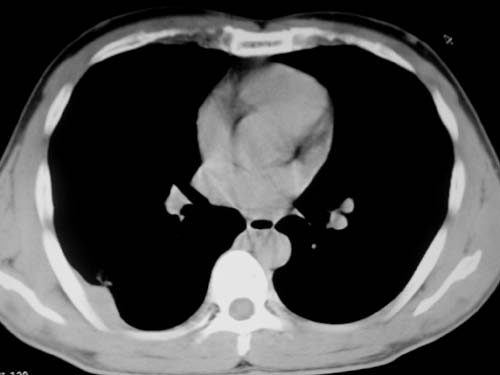

标题: CT19540: 31岁。自述结核性胸水治疗两个月后,在外院拍x线发 [打印本页]

标题: CT19540: 31岁。自述结核性胸水治疗两个月后,在外院拍x线发

右侧胸壁结节状软组织影伴相应肺叶内受侵,伴右侧胸腔积液。考虑:结核性可能大。

支持 右侧胸壁结节状软组织影伴相应肺叶内受侵,伴右侧胸腔积液。考虑:结核性可能大。

1、炎性病变,结核可能;2、右侧少量胸膜积液。

右侧胸壁结节状软组织影伴相应肺叶内受侵,伴右侧胸腔积液,结合临床,首先考虑结核。

考虑结核性胸膜炎,胸膜肥厚,不除外胸膜间皮瘤可能,建议复查。

1)考虑右侧结核性胸膜结节。2)右侧胸膜增厚+包裹性胸腔积液。

结核性脓胸、肺内结核?